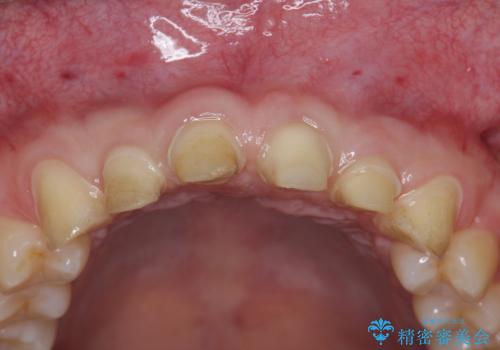

ただ、白いオールセラミッククラウンを製作・装着するのではなく、将来にわたり安定した状況を獲得するため、歯周外科を行い歯ぐきと周囲の歯槽骨の形態を整えていきます。

歯周外科を行ったことで、歯ぐきの形態や腫れが改善され、審美性だけでなく清掃性も大きく改善することができました。